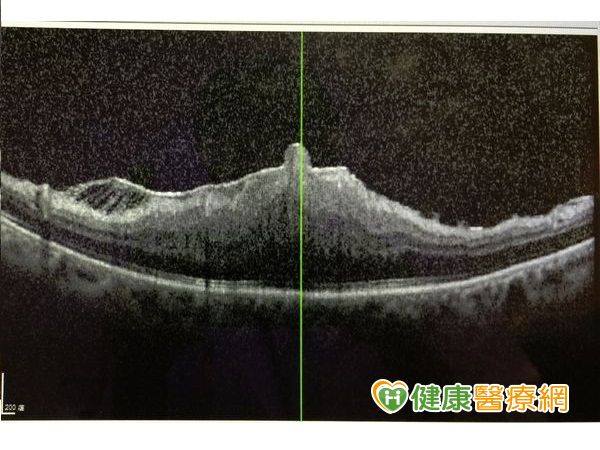

收治這名婦人的新竹馬偕醫院眼科主治醫師張聰麒表示,經由光學斷層掃描後發現,該名婦人的黃斑部皺摺相當堅厚,主要是因為眼球內部曾發炎導致,皺摺的位置就位於眼球正後方,黃斑部因為皺折拉扯成一團,視力僅有0.1,且不僅影響視力,更會造成視覺扭曲模糊。

(▼OCT切面可見其高高隆起,通常皺褶撕除後仍改善不多。)